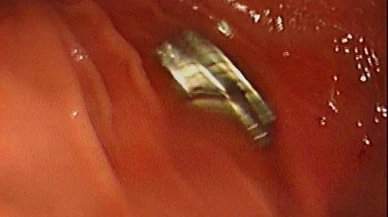

Mıknatıs Haberleri

Son Dakika Mıknatıs Haberleri

Bu sayfada güncel gelişmeleri takip edenler için Mıknatıs ile ilgili en son gelişmeler ve son dakika Mıknatıs haberleri sunulmaktadır. Mıknatıs ile ilgili tüm video, Mıknatıs fotoğrafları ve Mıknatıs haberleri